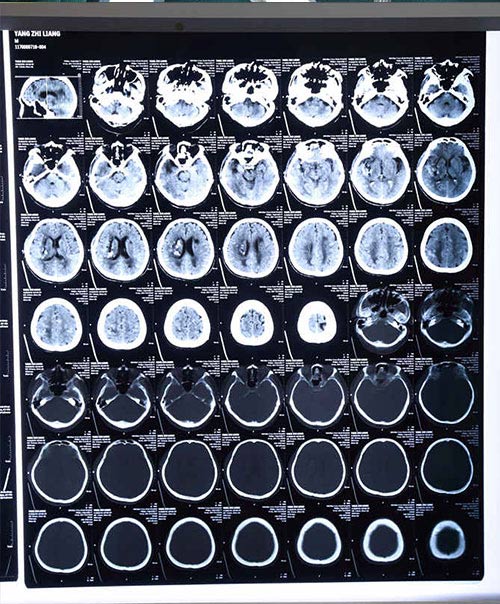

術(shù)后三天復(fù)查頭顱CT:血已經(jīng)全部清除干凈

術(shù)后第一天病人意識(shí)清楚,講話清晰,第二天可以吃東西,引流3天后血腫完全清除。目前楊志新老人生命體征平穩(wěn),各項(xiàng)指標(biāo)恢復(fù)正常。下一步病人需積極康復(fù),將致殘率降到最低。